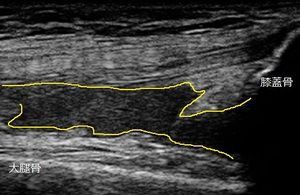

右ひざ 超音波長軸像 同部 1週間後

超音波観察の結果、右膝蓋骨(お皿)の上部には内出血が貯留している様子が認められました(上部左画像の

黄色線内)。

いきます。1週間後、施術効果を客観的に評価するために超音波観察を実施し、内出血の減少を確認しました

(上部右画像の黄色線内)。